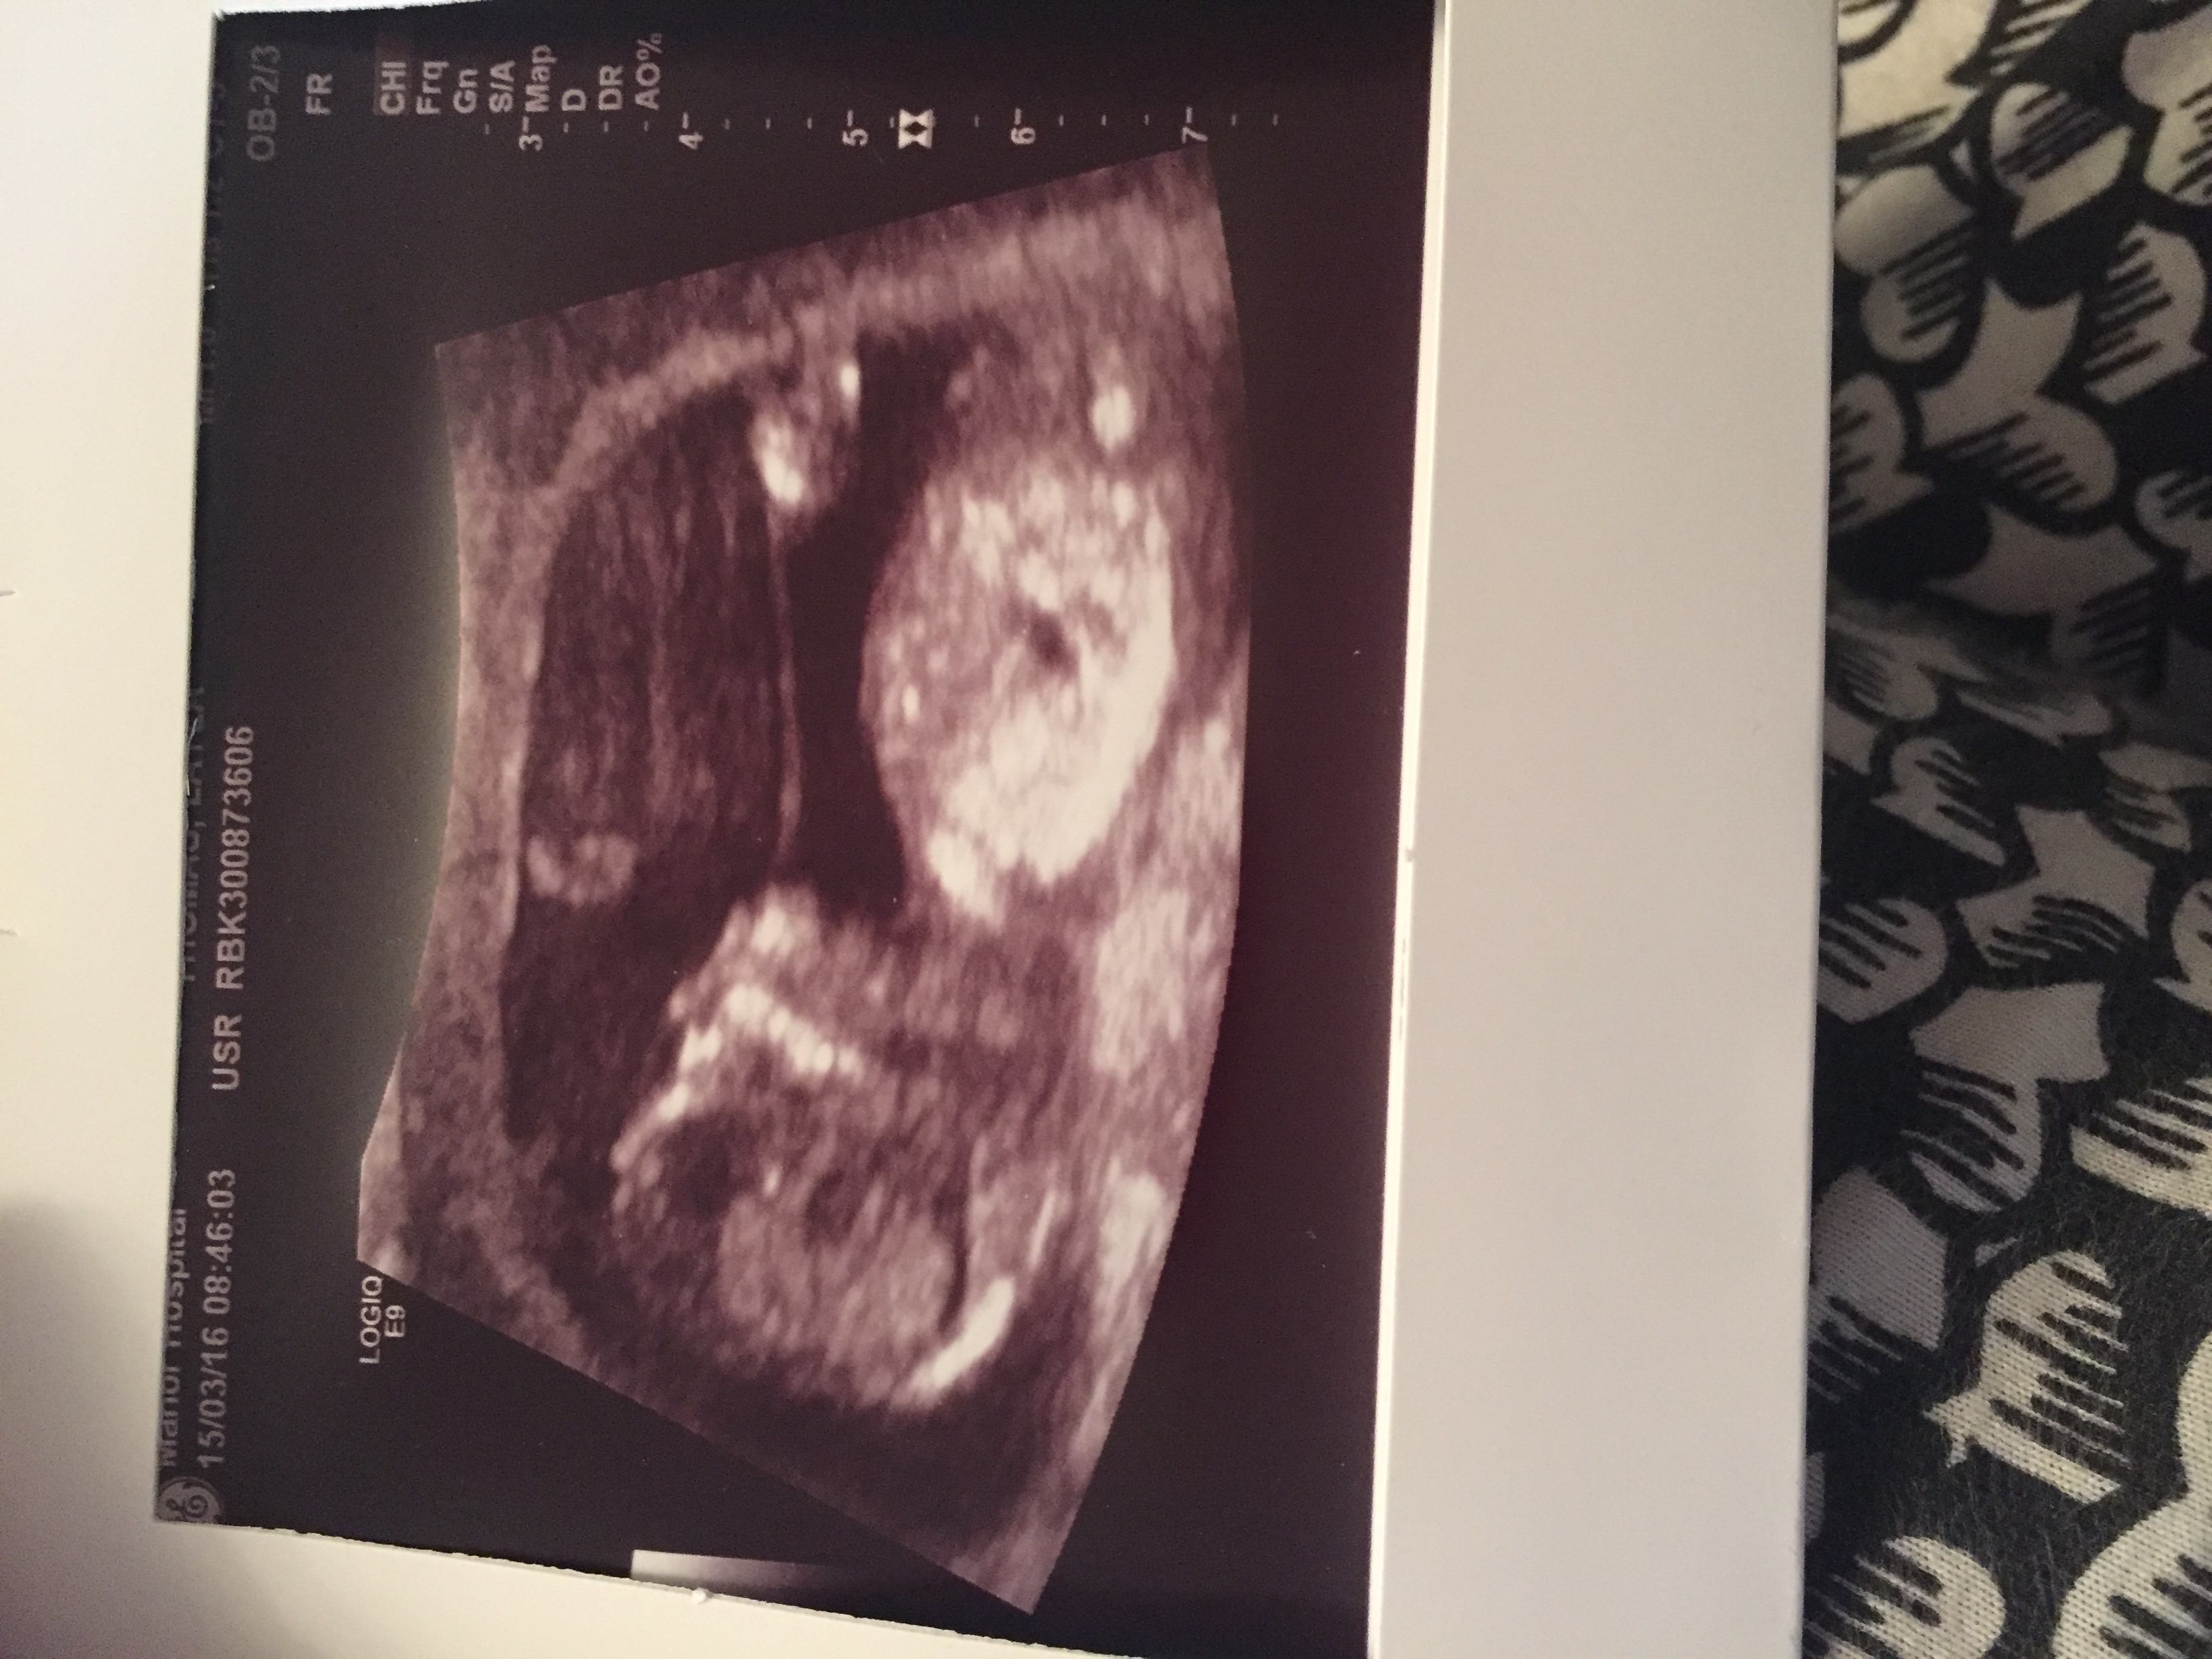

I'm just intrigued. Gender scan booked for two weeks , this was taken at exactly 13weeks.

I'm thinking another boy as the scan looks pretty similar to my son

Can't see any Gender clues x

No nub.